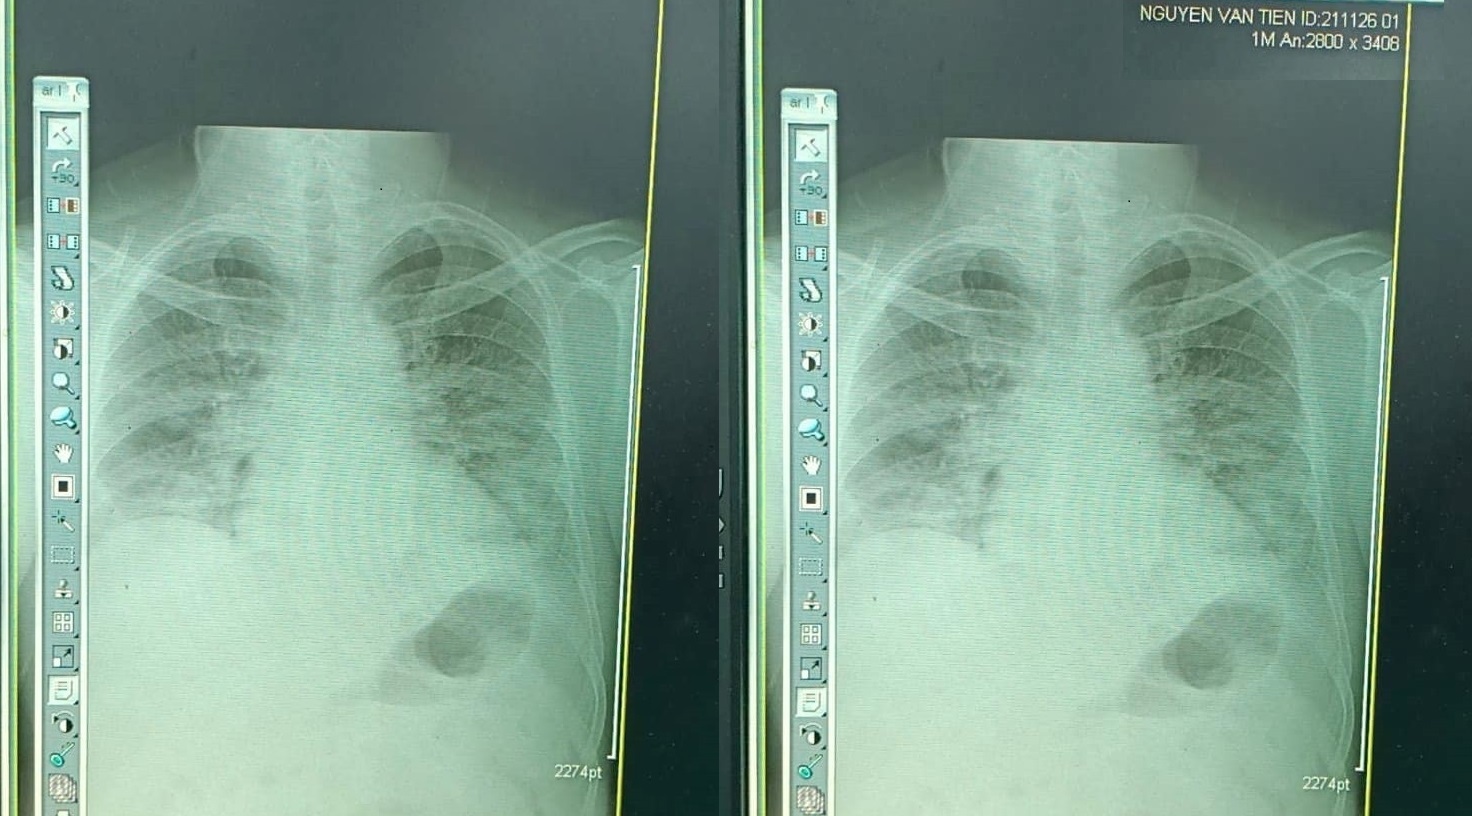

Buổi sáng ngày thứ 7 của bệnh, ông cảm thấy mệt khi đi lại, hơi thở dồn dập, mắt mờ tối sầm. Chỉ số SpO2 đo nhiều lần vẫn dưới 85%. Ông nhanh chóng được cấp cứu, cho thở oxy và tiến hành hàng loạt xét nghiệm. Kết quả X-quang phổi cho thấy trắng xoá gần hết 2 phế trường.

![]() |

| Kết quả X-quang phổi của bác sĩ Nguyễn Văn Tiến. Ảnh: FBNV |

Ngày thứ 12, kết thúc đợt 2 trị liệu, X-quang phổi vẫn trắng xóa, viêm đặc thuỳ dưới phổi. “Hết hy vọng rồi, cơn bão Cytokine đã càn quét, rồi đây chuẩn bị hôn mê, đặt nội khí quản, chạy ECMO”, ông dự liệu trước cho bản thân mình.